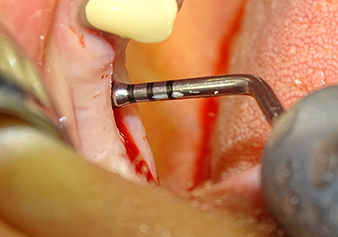

Le site implantaire est élargi à 3,0 mm à l'aide de l’insert I3A (puissance 100 %, fluide de refroidissement 80 %). Les repères de profondeur garantissent de ne pas dépasser une certaine profondeur pendant la préparation.

Fig.5 : À l’étape suivante, le site implantaire est élargi à 3,0 mm à l'aide de l’insert I3A (puissance 100 %, fluide de refroidissement 80 %). Les repères de profondeur garantissent de ne pas dépasser une certaine profondeur pendant la préparation.